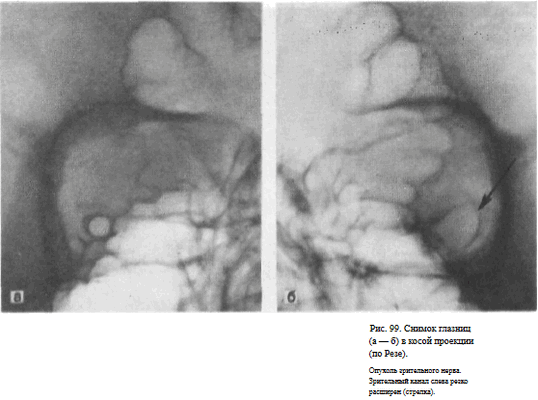

СНИМОК ГЛАЗНИЦЫ В КОСОЙ ПЕРЕДНЕЙ ПРОЕКЦИИ (СНИМОК ЗРИТЕЛЬНОГО КАНАЛА ПО РЕЗЕ)

Назначение снимка. Основное назначение снимка — получение изображения зрительного канала, Как правило, для оценки ширины и формы канала прибегают к последовательной съемке правой и левой глазницы.

Голову поворачивают в сторону и укладывают таким образом, чтобы к экспонируемой половине кассеты прилегали надбровная дуга, скуловая кость и кончик носа, а в центре ее находилась исследуемая глазница. Срединная сагиттальная плоскость головы образует с плоскостью стола угол в 40—50°, открытый кзади. Кассета размером 18Х 24 см располагается на столе в поперечном положении.

Поочередно экспонируют правую и левую половину кассеты, перекрывая неиспользуемую половину листом просвинцованной резины. На кассету накладывают неподвижную отсеивающую решетку.

Пучок излучения направляют отвесно на наружный угол глаза исследуемой стороны (рис. 97).

Информативность снимка. На снимке отображается зрительный канал, имеющий обычно неправильно-округлую форму с четкими резкими контурами. Видны также вход в глазницу, решетчатые ячейки (рис. 98, а, б). Расширение зрительного канала, возникающее при опухолях зрительного нерва, как правило, может быть достоверно выявлено только путем сравнительного анализа снимков правой и левой глазницы (рис. 99, а, б). Поэтому снимки глазниц в косой проекции по Резе всегда следует производить с обеих сторон.